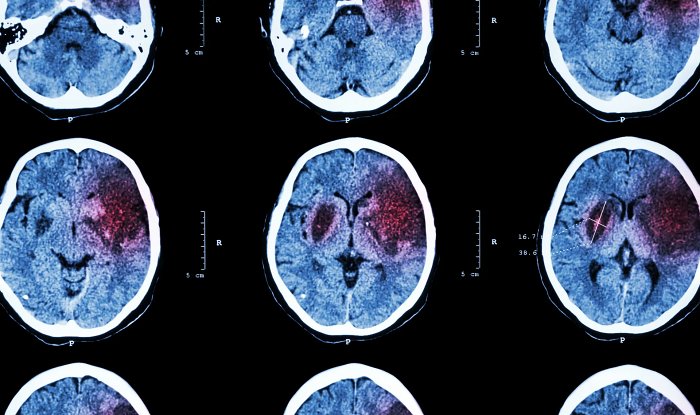

Диагностика инсульта крайне сложна из-за специфики заболевания — например, в 25 % случаев характерных внешних симптомов просто нет. Смертность от неверно определенного инсульта в 30 раз выше смертности от неустановленного вовремя сердечного приступа. Симптомы инсульта легко спутать с десятками других заболеваний и отклонений, поэтому необходимость в автоматической диагностике весьма велика.

Новая модель прошла обучение на 143 тыс. медицинских карт пациентов больниц Флориды, в выборку вошли люди всех рас и возрастов. Тестирование показало, что она может выявить инсульт или определить, что он случался в прошлом, с точностью 84 %. У прочих моделей этот показатель не превышает 30 %. Однако авторы разработки настаивают, что их модель пока не пригодна для автономного применения, ее следует использовать вместе с другими методами.